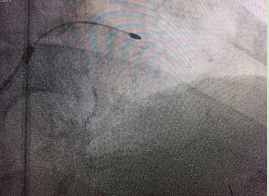

术后

“由于病人的左主干及三支血管均有不同程度的病变,为了安全起见,我们采取了分步实施手术的原则,先处理了两支钙化较严重的血管。”袁小蓉表示,令人欣慰的是,第一次手术后老人胸闷胸痛症状迅速缓解,术前在医院过道上走二三十米就感到明显胸痛,术后第二天便在病房内随意走动,术后第三天就可以到医院附近走动而无明显胸闷胸痛等不适。

数天后,我院心血管内科对病人的另外一支病情稍轻的血管施行了普通冠脉内支架植入手术,手术过程顺利,术后老人病痛完全解除。至此,困扰陈大爷3年的胸痛顽疾得以消除。